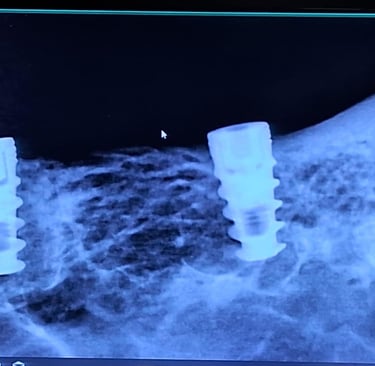

Single Sitting RCT

RCT is done in one visit, usually when the infection isn’t severe. It includes cleaning, shaping, disinfecting, and sealing the canal, followed by final restoration.